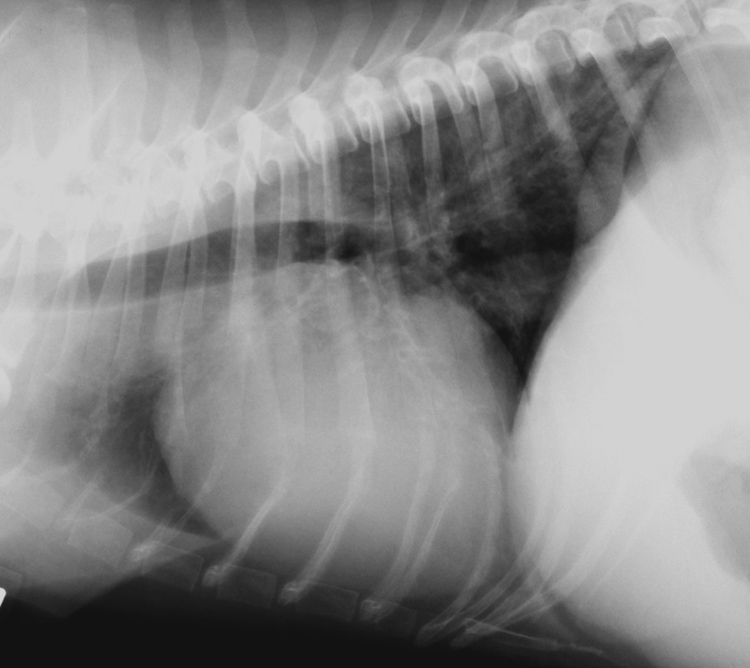

Reasons for RHF-

Secondary to LHF

Pericardial disease (effusion, inflammation)

HW (dirofilariasis, angiostrongylus)

Tricuspid valve insufficiency: - secondary to mitral valve insuff (MOST COMMON), endocardosis (dysplasia), Cor pulmonale- HW, Pulmonary thromboembolism), Endocarditis (less common tin tricuspid than in mitral and aortic), Ruptured chordae tendinae or papillary muscle

Reasons for LHF

Mitral valve insufficency - endocardosis (MOST COMMON), endocorditis, ruptured chordae tendinae

Cardiomyopathy